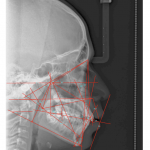

• A través de sencillas pero poderosas herramientas se pueden hacer trazados cefalométricos que permitan al médico observar, analizar y/o diagnosticar detalladamente y con mayor rapidez y confiabilidad.

- Ricketts 33